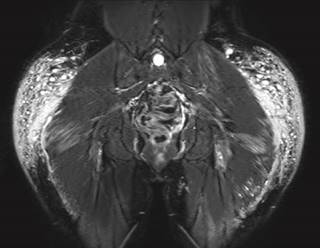

Paciente de 30 años con antecedentes de aplicación de modelantes en las regiones glúteas hace 10 años. Desde hace tres años presenta dolor en ambas piernas, con zonas induradas y cambios de coloración. Se le realizó resonancia magnética de las regiones glúteas y piernas identificando imágenes globulares y lineales irregulares de comportamiento isointenso en el T1, hiperintenso en el T2, hiperintenso en las secuencias de saturación grasa (Fat-Sat) y en STIR (Short Inversion Time Inversion Recovery) con compromiso de los tejidos blandos superficiales y de los planos musculares que afectan a los glúteos mayor y medio (Figuras 1 y 2).

Figura 1: Resonancia magnética regiones glúteas. Axial STIR. Imágenes globulares y lineales con infiltración de los músculos glúteos mayores y medios compatibles con modelantes.